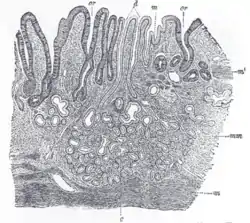

![]() Gastric glands shown at c and their ducts at d | |